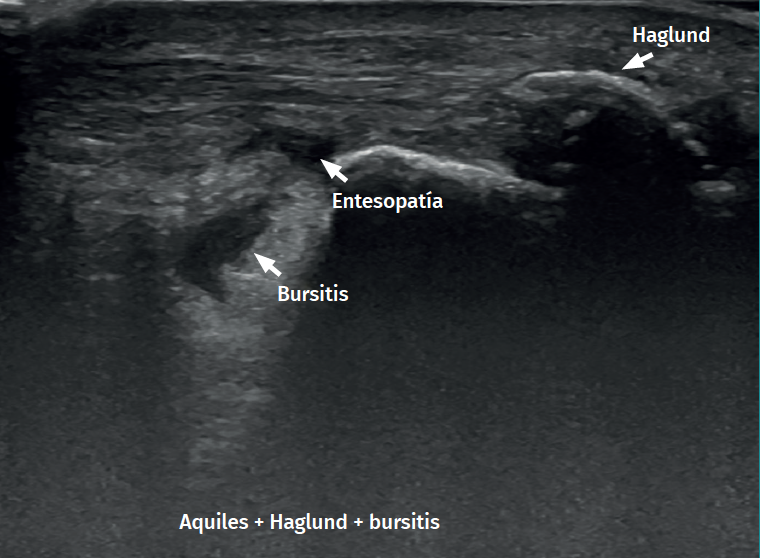

Figure 1. Insertional Achilles tendinopathy associated to retroachilleal bursitis and Haglund deformity.

With regard to the pathological ultrasound findings (Table 1), non-insertional Achilles tendinopathy (2-6 cm from the calcaneal insertion) (Figure 1) is characterized by a spindle-form thickening of the tendon area, hypoechoic areas and disruption of the fibrillar pattern that can correspond to degeneration or partial rupture(24,28). Increased vascularization of the peritendinous ventral portion may also be present(5,6,30).

However, in the chronic forms of insertional Achilles tendinopathy or enthesopathy (present in the distal 2 cm of the tendon), we can observe calcifications within the tendon in the form of traction enthesophytes or at the insertion site in the form of spurs. These conditions are often associated to alterations of the retroachilleal bursa(5,31)(Figure 2).

In isolated peritendinitis, ultrasound shows a normal tendon surrounded by fluid in the form of a hypoechogenic halo. In chronic presentations we observe a hypoechogenic thickened paratendon usually associated to tendinosis(32).

Retrocalcaneal bursitis is characterized by an increased volume of the bursa, with the possible association of Haglund deformity(25). In the case of retroachilles or superficial calcaneal bursitis we can identify fluid between the skin and the Achilles tendon(5).